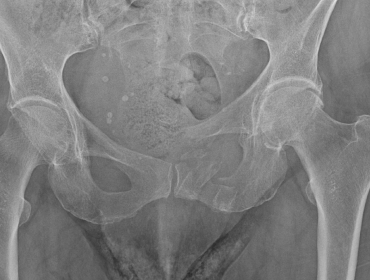

Beckenchirurgie wieder am Klinikum Hochrhein etabliert

Mit dem Neustart von Dr. med. Holger Knorn ist die spezialisierte Beckenchirurgie wieder ein fester Bestandteil unseres Leistungsspektrums. Ein aktueller Fall zeigt, wie wichtig diese Expertise im Haus ist.